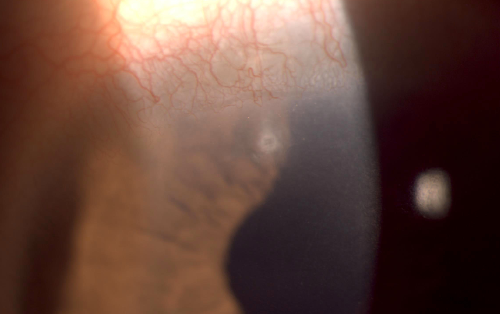

첫번째 사진은 눈꺼풀을 뒤집어서 이물이 있는지 확인한 것입니다.

그런데 상부 각막에서 과거 백내장 수술 후 남은 실밥이 노출되어 있는 것이 확인되었습니다.

이물감으로 눈을 만지는 바람에 상안검판에 충혈이 있고

상부 윤부에 염증소견이 있지만 심하지는 않았습니다.